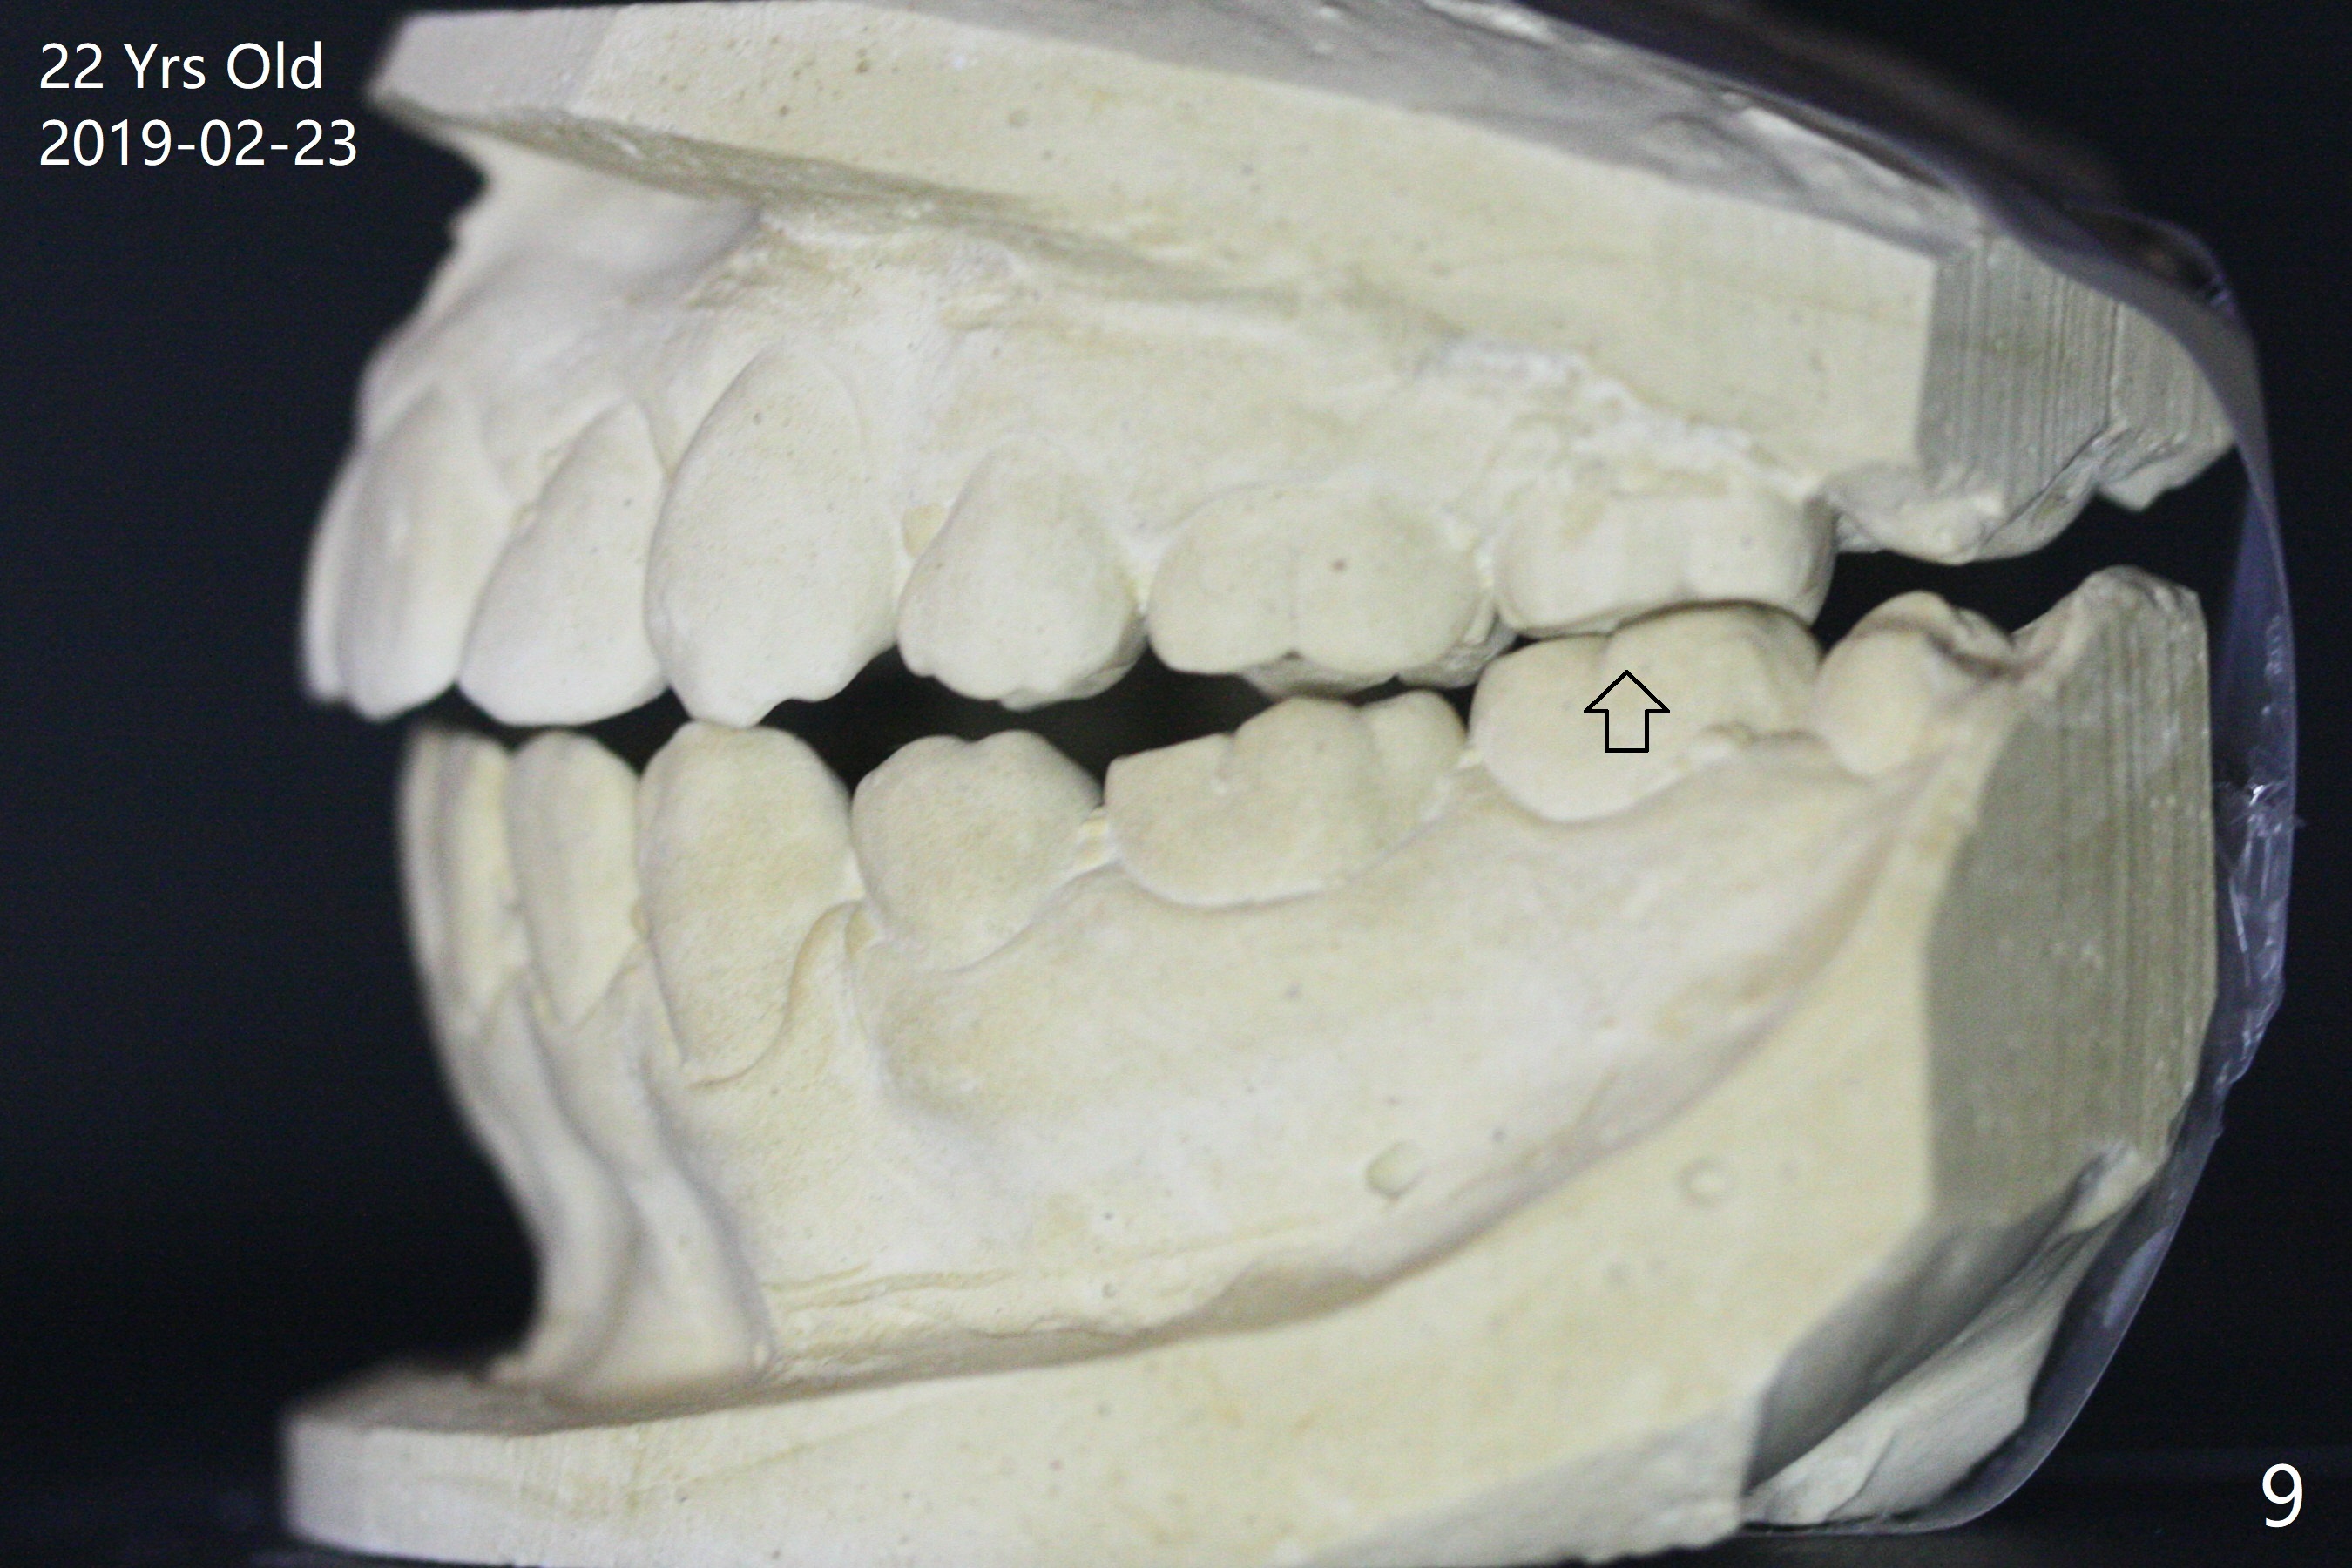

A 16-year-old man has severe crowding, but the open bite is ignored (Fig.1,4,7,10,13). The orthodontic treatment lasts 4 years 5 months, including failure to return for a period of time. The open bite seems to have been corrected (Fig.2, 5, 8, 11, 14). Suction down retainers are provided. In less than 2 years, the patient returns requesting remaking retainers. It appears that open bite relapses (Fig.3,6,9,12,15), as related to supraeruption of the lower 2nd molars (Fig.6,9 arrows). The latter is apparently associated with the erupting 3rd molars.